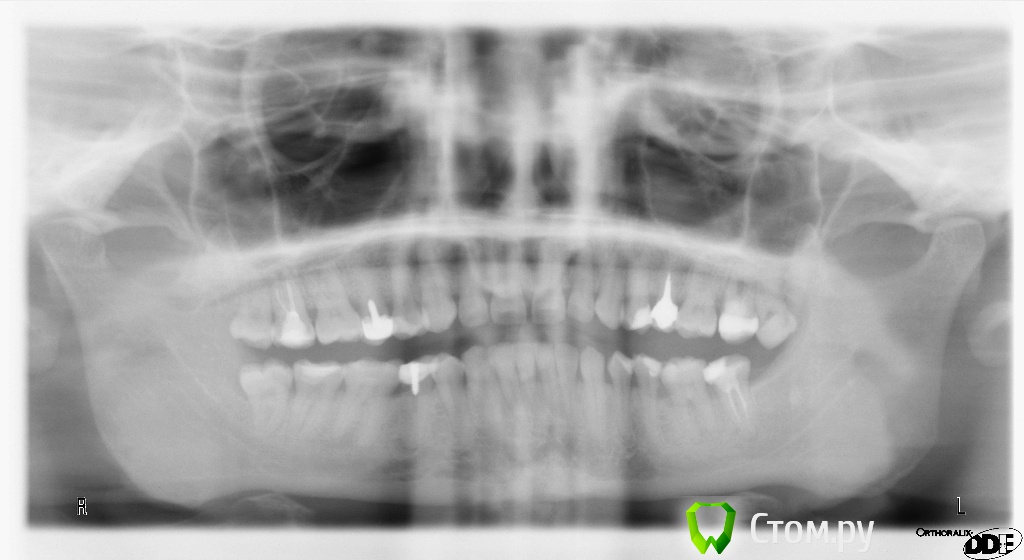

alena341 Опубликовано 9 декабря, 2013 Поделиться Опубликовано 9 декабря, 2013 Здравствуйте, хотела узнать ваше мнение по проблеме: На следующий день после замены штифта в 25 зубе, началось легкое подергивание нижнего века правого глаза, которое периодически возобновляется до сих пор, уже несколько месяцев. Знаю, что это скорее всего совпадение, но все же хотела узнать мнение специалистов. Могли ли стоматологические операции спровоцировать появление подергивания нижнего века? Выкладываю два панорамных снимка со старым и новым штифтом, по которым видно, что новый штифт существенно длиннее. При смене штифта перепломбировки каналов не производилось. Лечение проводилось под местной анестазией. При следующем посещении была также произведена смена коронки. Спасибо за ответ!с уважением,Ольга Ссылка на комментарий

shishok Опубликовано 9 декабря, 2013 Поделиться Опубликовано 9 декабря, 2013 А прицельного снимка нет?Удаляйте все оставшиеся восьмые+срочно перелечивать 45(это для начала) 1 Ссылка на комментарий

shishok Опубликовано 10 декабря, 2013 Поделиться Опубликовано 10 декабря, 2013 (изменено) Нет,связи возможно и нет,хотелось бы посмотреть пломбировку канала(на ОПТГ плохо видно).А с 28 расстаньтесь поскорее,может он даёт какие-то боли(не резко выраженные),которые вызывают подёргивание века.ИМХО Изменено 10 декабря, 2013 пользователем shishok Ссылка на комментарий